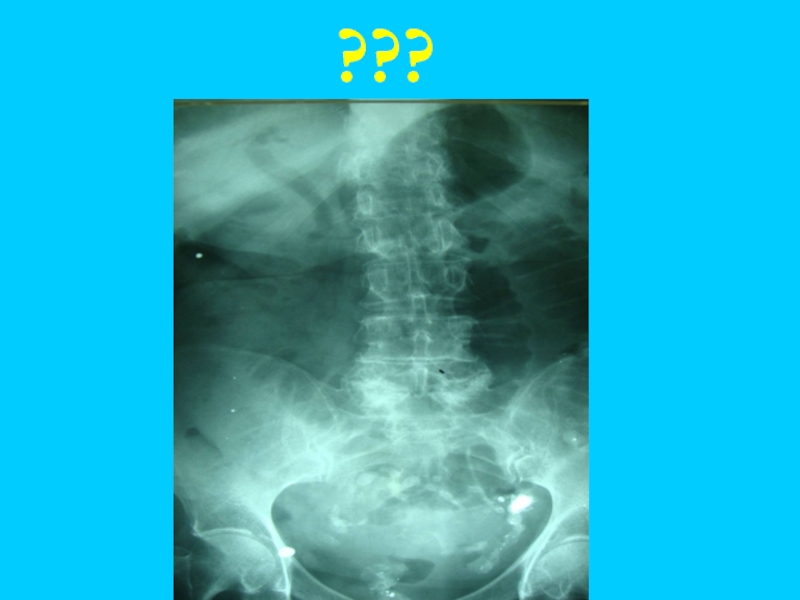

Слайд 68Рентгеновское иссле-дование обязательно всем больным с ОКН.

Выполняется обзор-ная R-скопия или R-графия

в вертикаль-ном положении в прямой проекции

Слайд 69 При невозможности произвести исследование в положении стоя при тяжелом состоянии

больного, допустима латеропозиция (положение лежа на боку)

Слайд 70Арки и чаши Клойбера, уровни жидкости

Слайд 71Чаши и арки Клойбера- горизонталь-ные уровни жидкости с куполообраз-ным просвет-лением

Слайд 72является бесспорным рентгенологическим признаком ОКН.

и контурируемых керкринговских складок (положительный симптом Кейси

или «рыбьего скелета»)

Слайд 73В более ранних ста-диях КН рентгено-логически может определяться скоп-ление газа (без

уров-ня жидкости) в петле кишки соответст-венно определяемому клинически симптому Валя-симптом Гинтце (Hintze)

Слайд 74Скопление газов в виде арки –

симптом Штирлина